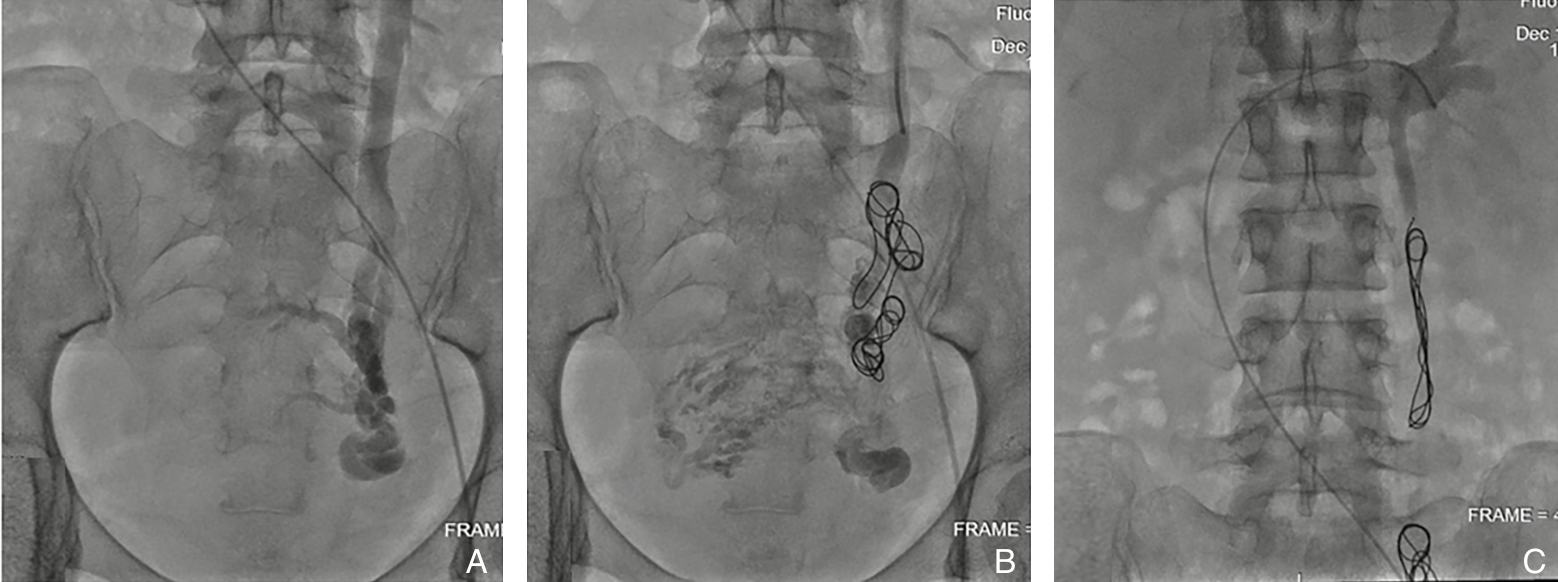

2025, 34(12):2672-2678. doi: 10.7659/j.issn.1005-6947.250564

摘要:背景与目的 盆腔静脉疾病(PeVD)是慢性盆腔痛的重要血管性病因,其中卵巢静脉反流最为常见。卵巢静脉栓塞已被证实具有良好疗效,但在实际应用中,栓塞范围、弹簧圈数量及是否需要联合处理其他盆腔静脉病变等技术细节尚缺乏统一共识。本研究旨在评估采用简化策略的左侧卵巢静脉弹簧圈栓塞联合硬化剂注射治疗PeVD的短中期疗效及安全性。方法 回顾性分析2023年2月—2024年2月收治的55例PeVD女性患者,均经超声、CT静脉造影及静脉造影确诊,并接受左侧卵巢静脉弹簧圈栓塞联合硬化剂治疗。随访1、3、6、12个月,比较术前与术后疼痛视觉模拟评分(VAS)、症状改善情况及并发症发生情况;术后3个月行超声评估卵巢静脉闭塞及盆腔静脉改善情况。结果 所有患者均获得技术成功。术后12个月VAS由术前的7.2±1.2降至2.9±2.8(P<0.01),81.8%患者症状改善,其中50.9%症状完全消失。术后3个月超声显示卵巢静脉均完全闭塞,左侧宫旁静脉直径较术前显著减小[(7.1±1.4)mm vs. (3.4±0.7)mm,P<0.001]。总体并发症发生率为14.5%,以一过性盆腔痛为主,均经对症处理后缓解。结论 采用简化栓塞策略的左侧卵巢静脉弹簧圈栓塞联合硬化剂注射治疗PeVD具有良好的短中期疗效和安全性,可作为以左侧卵巢静脉反流为主患者的有效微创治疗方案。